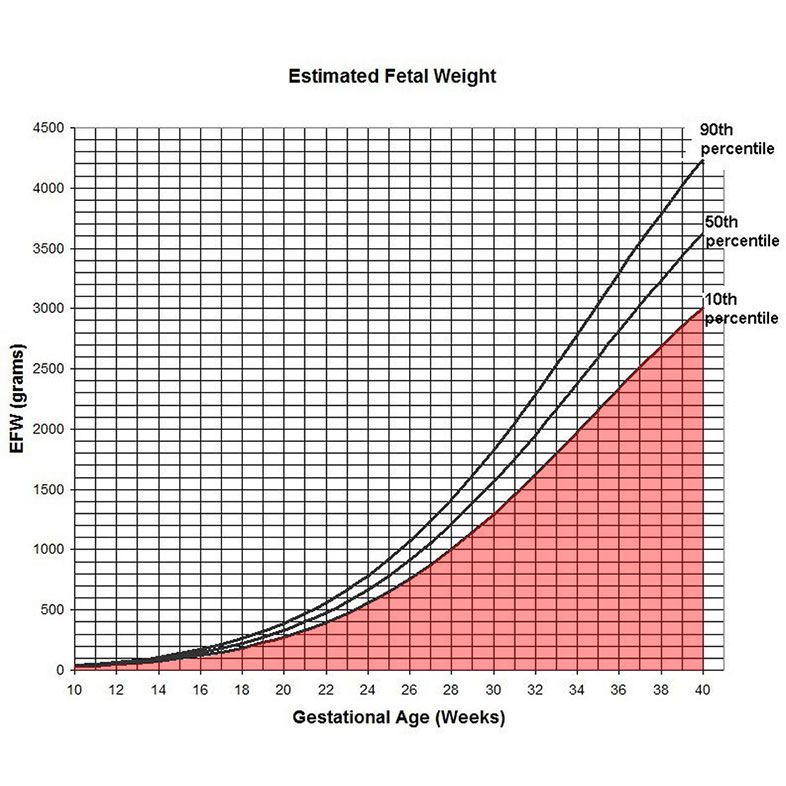

Perform ultrasound estimation of fetal weight (EFW),

Graph showing normal fetal weight bounds throughout the pregnancy